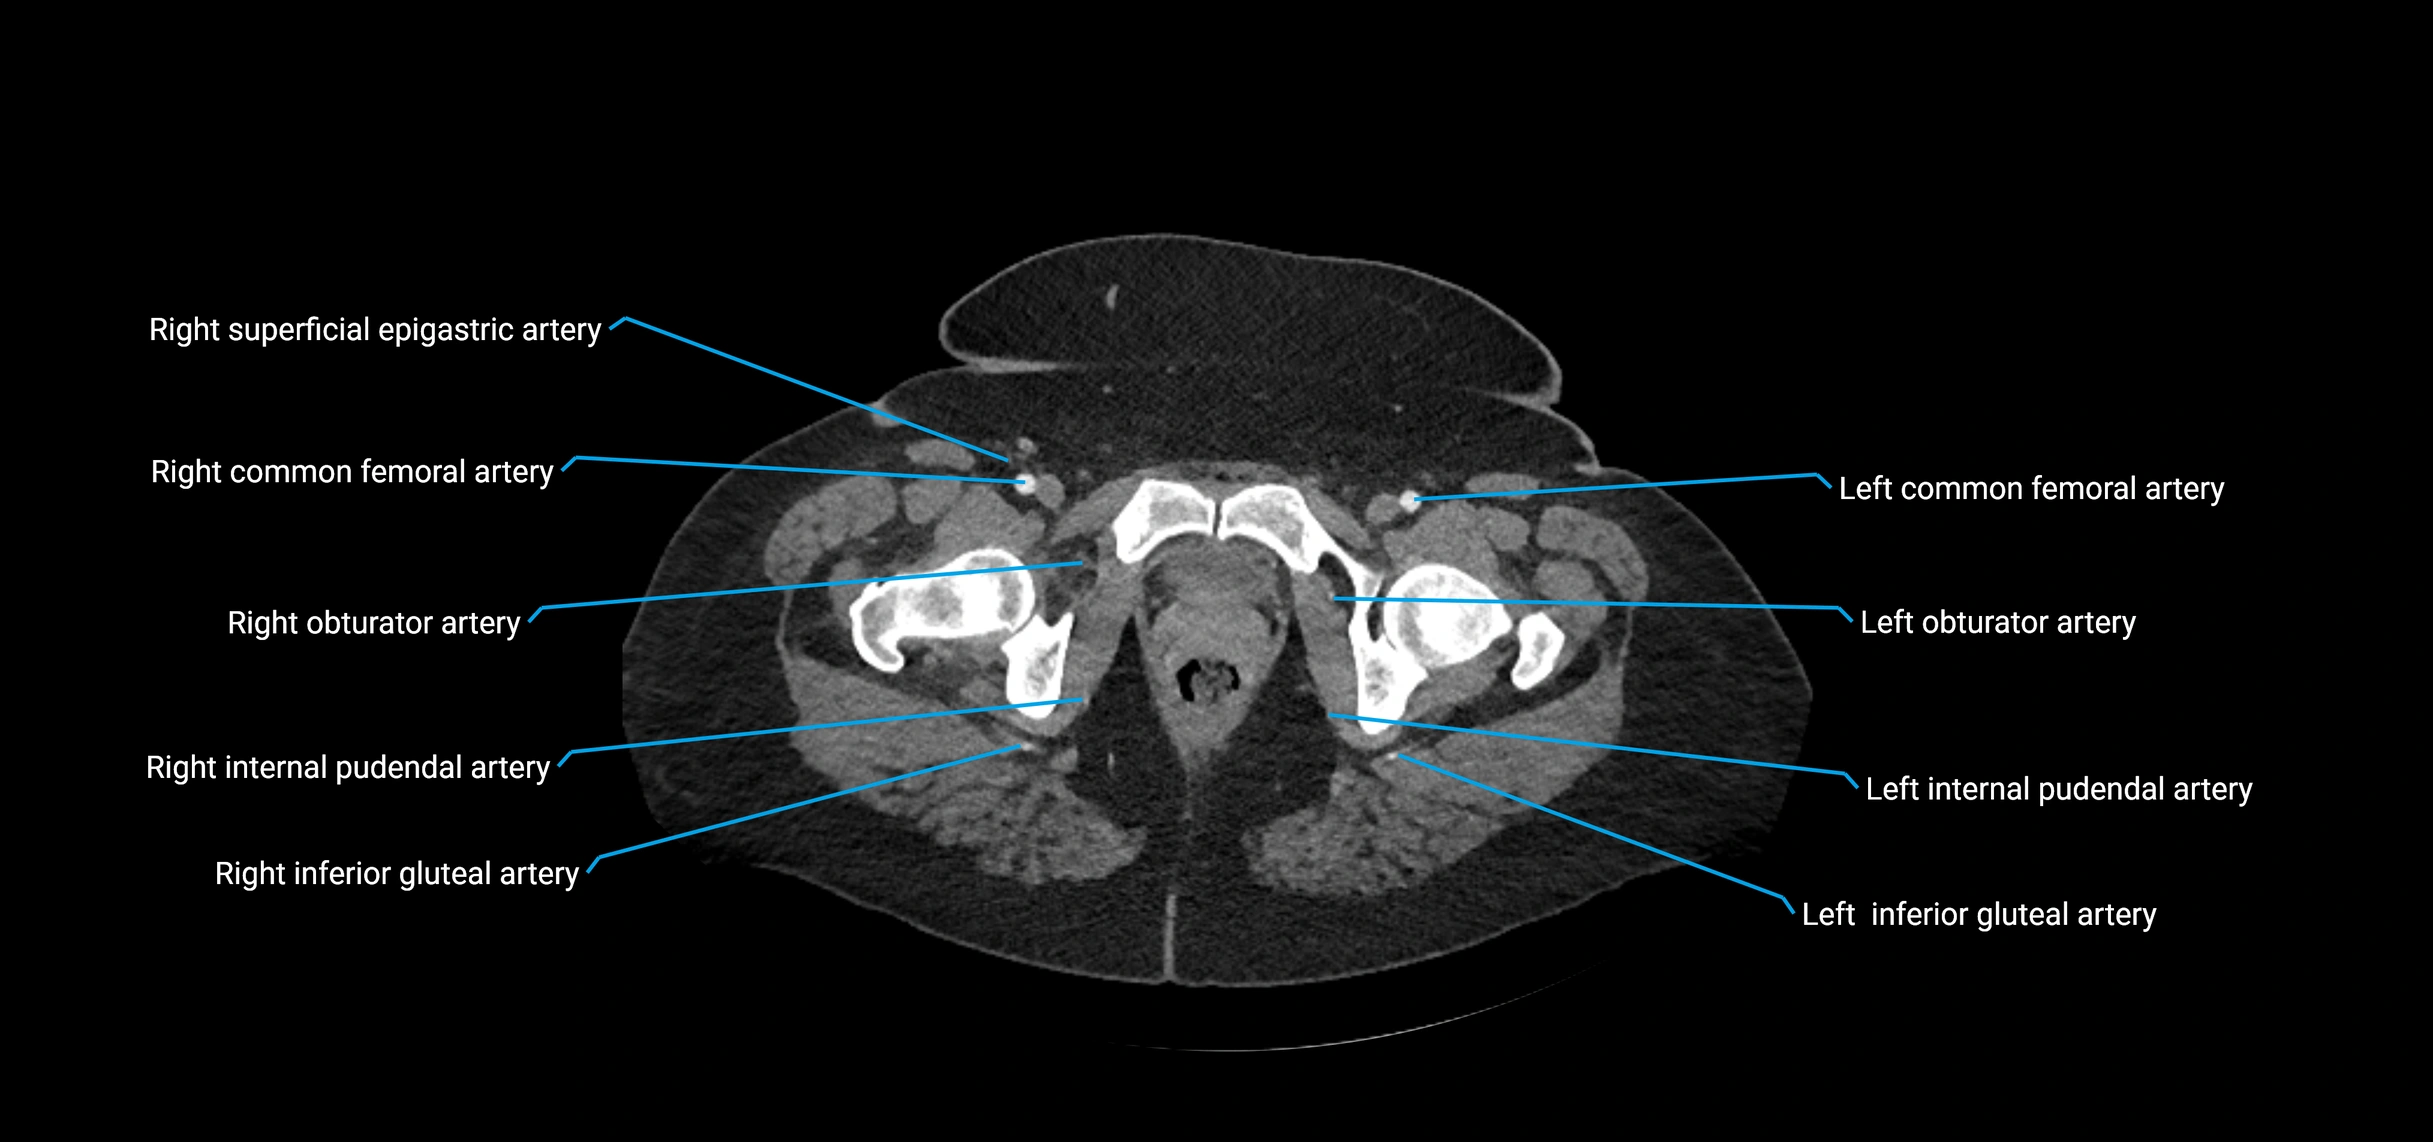

Contrast-enhanced CT (CTA):

• Gold standard for abdominal aortic imaging

• Provides excellent detail of lumen, wall, aneurysm, thrombus, and branch vessels

• Multiplanar and 3D reconstructions help in aneurysm measurement, stent graft planning, and dissection evaluation

• Detects acute rupture, traumatic injury, or occlusion with high sensitivity